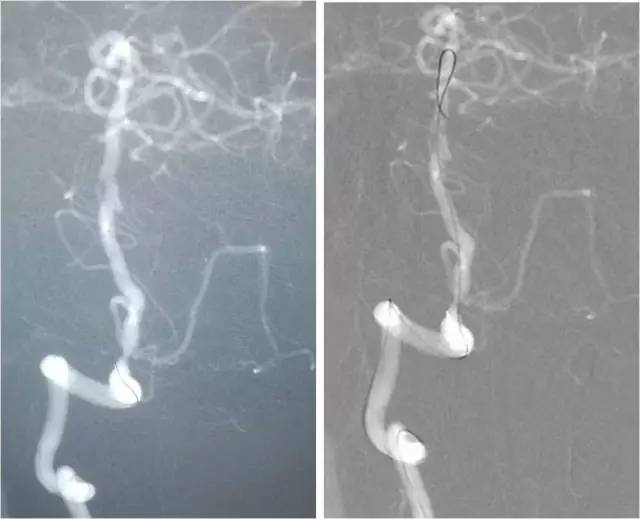

DSA:右大脑中动脉闭塞。左大脑前动脉A1段缺如。左胚胎型大脑后动脉。右椎动脉优势,右椎动脉V1及V4段重度串联狭窄。左椎动脉起始段狭窄,V4段闭塞。患者造影过程中存在一定程度不自主运动,故图像显影较差(图3-6)。

图3

图4

图5

图6